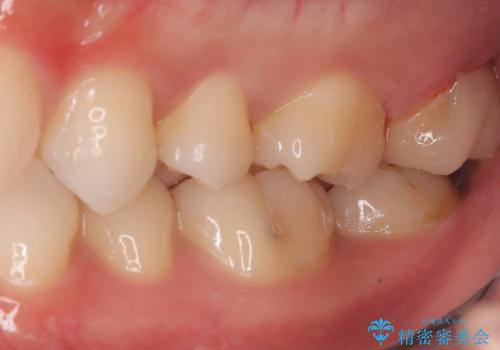

左上一番奥の歯の頬側に実質欠損を伴う虫歯が存在したため、セラミックインレーでの治療となりました。

上顎左側第二大臼歯頬側面から遠心面、咬合面にもう蝕が波及していたためアンレー形態となりました。

清掃しずらい箇所ではあるため、汚れが付きづらい適合性のよいセラミック素材を選択しました。

セラミックアンレーセット時、ラバーダム防湿を行っています。